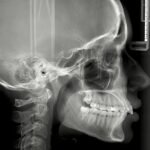

• Kraniogram: Snimka lubanje za planiranje ortodontskih tretmana.